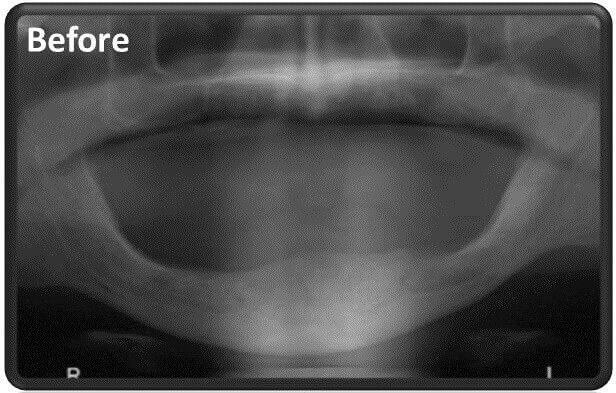

כאשר מגיע אדם לטיפול וצריך לעבור השתלת שיניים בלסת שלמה הוא עובר בשלב הראשון אבחון ע”י הדמייה תלת מימדית במכשיר CT, המאפשר לרופא השיניים להבין מה מצב הלסת שלו:

צילום CT יכול להראות לרופא השיניים מה בדיוק נעשה והאם שווה להשאיר את אותם שתלים דנטליים או שעדיף כבר להוציא אותם וליצור את כל מערכת השתלים הדנטליים מחדש.